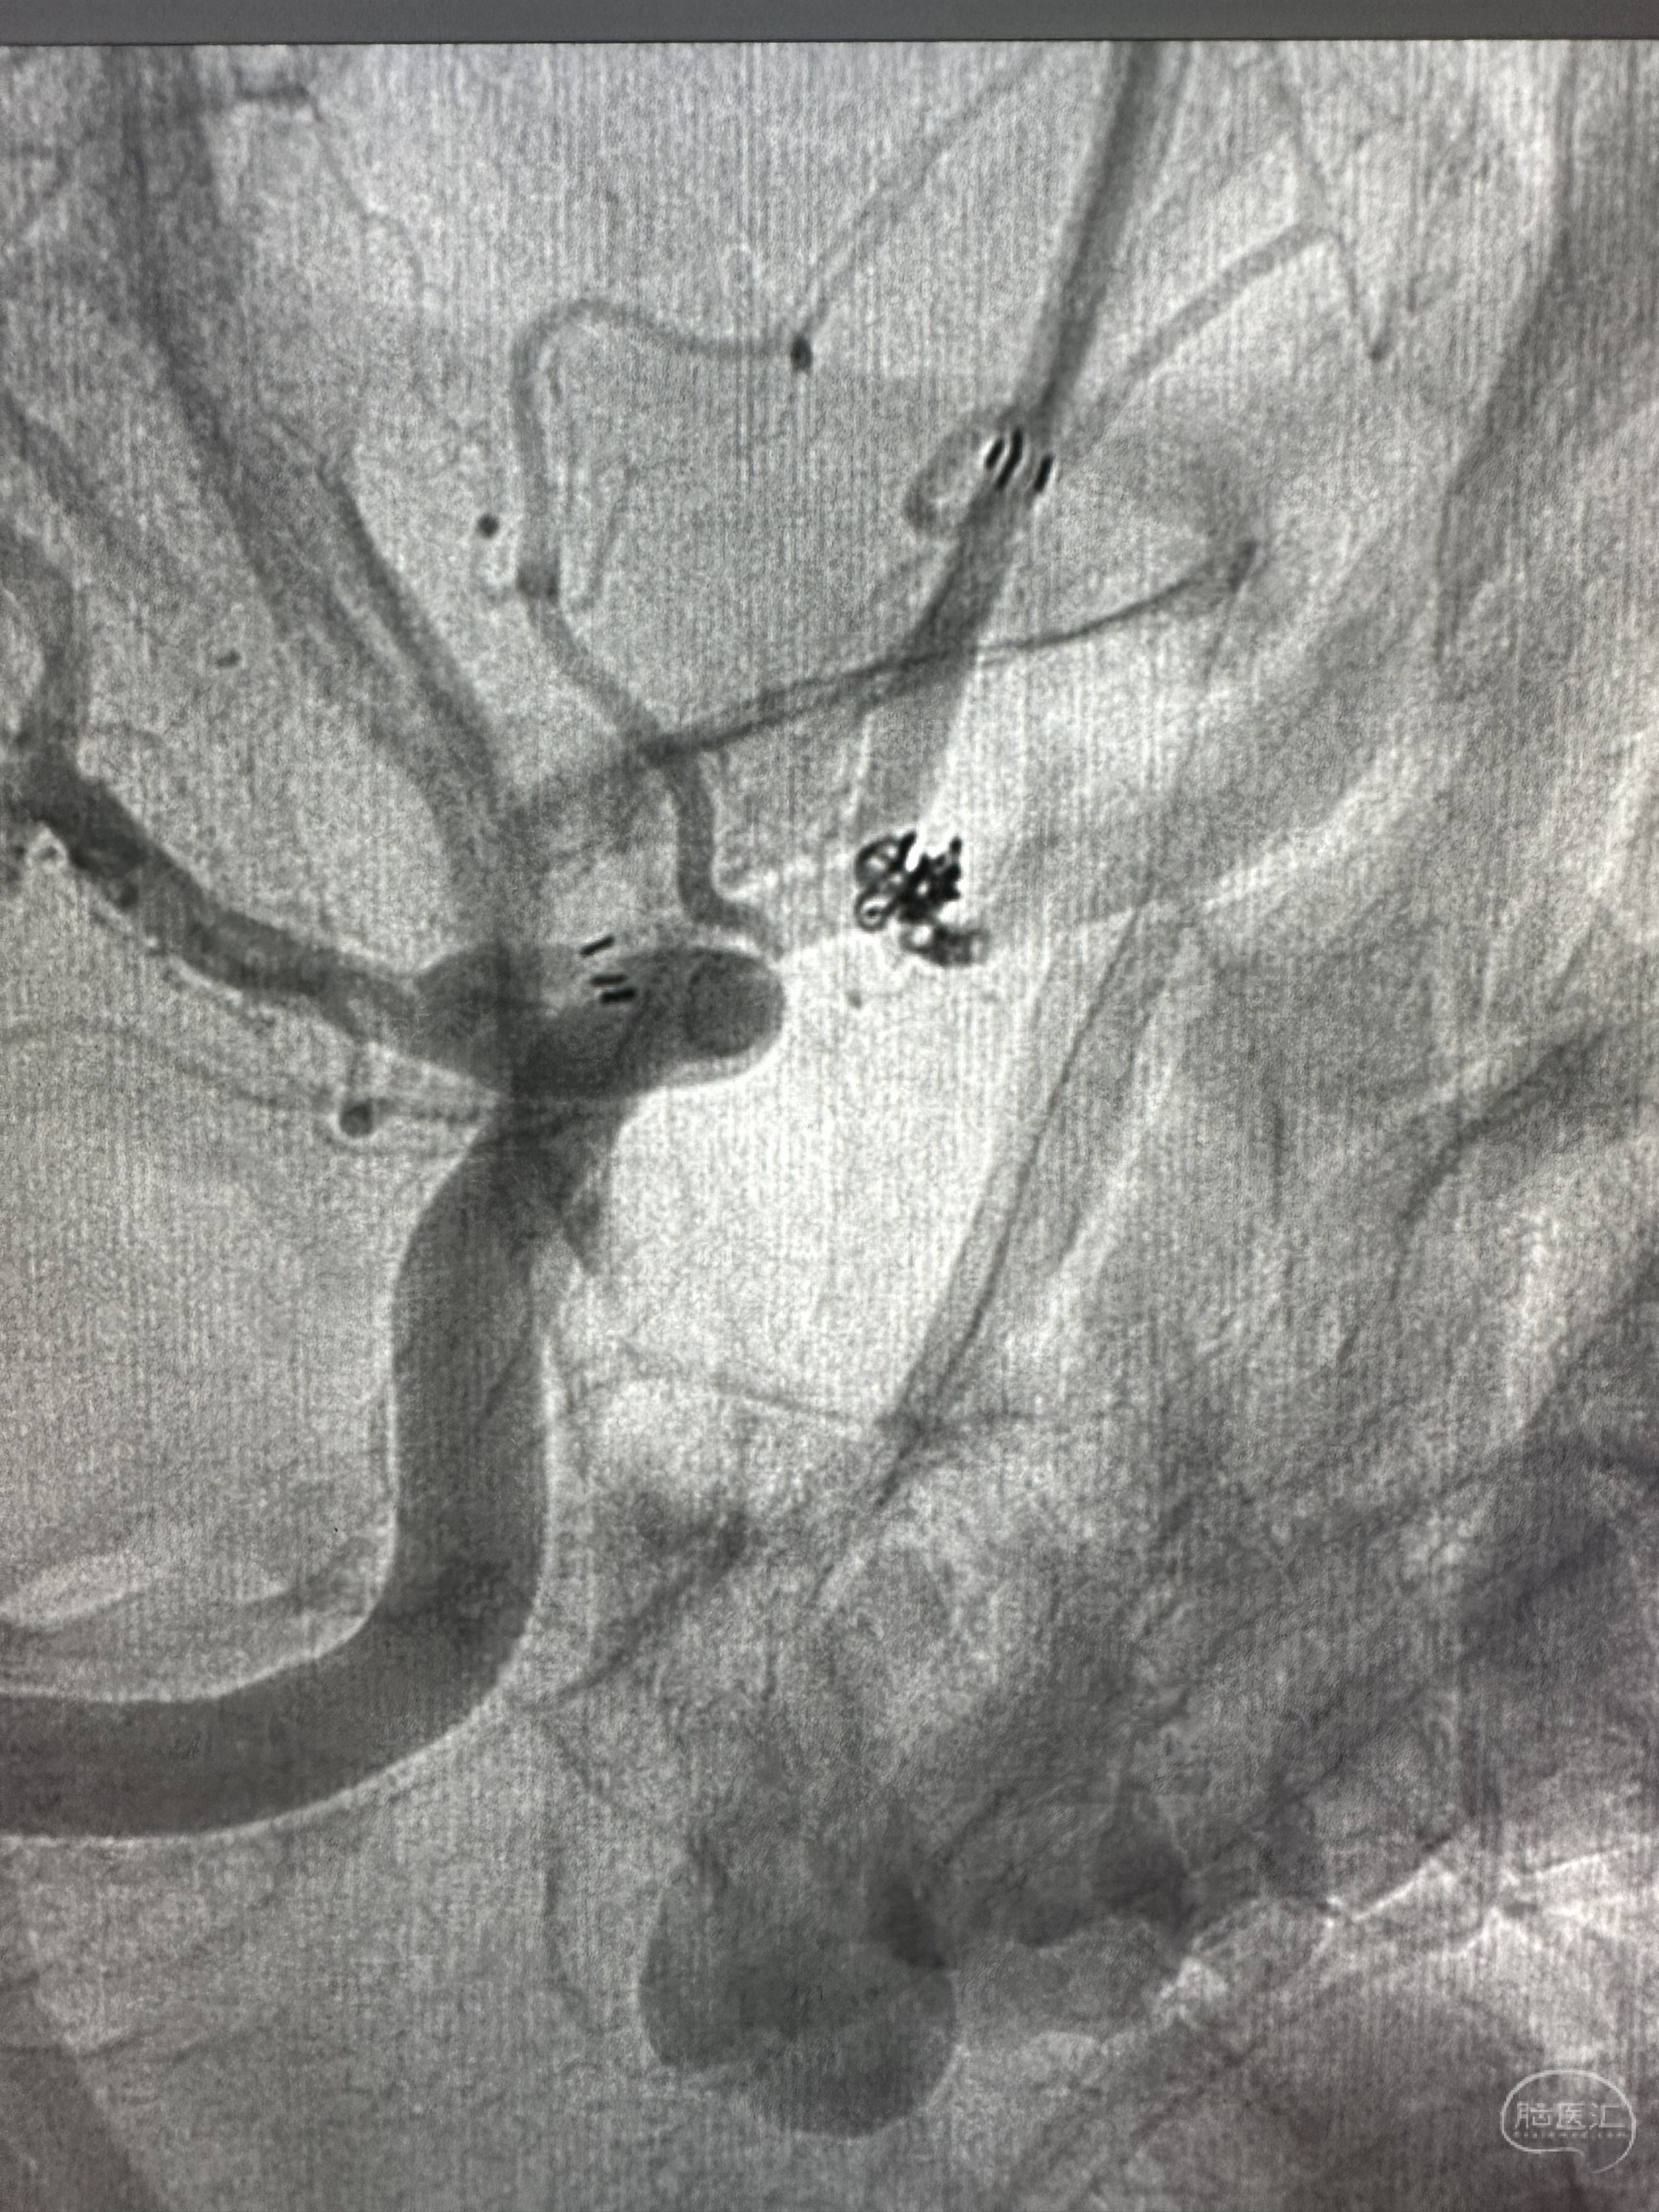

Plus支架导管到位,enchon 10直头小心接近动脉瘤,动脉瘤显影不太好

微导管到位后

第一枚圈填塞后,换了一个角度造影发现有点出血

补了一个圈,同时释放EP 2支架4*21的支架

再次造影未见出血,准备撤出微导管的时候,一个圈跑出来了,但是还是稳得住

果断再次补了一个圈